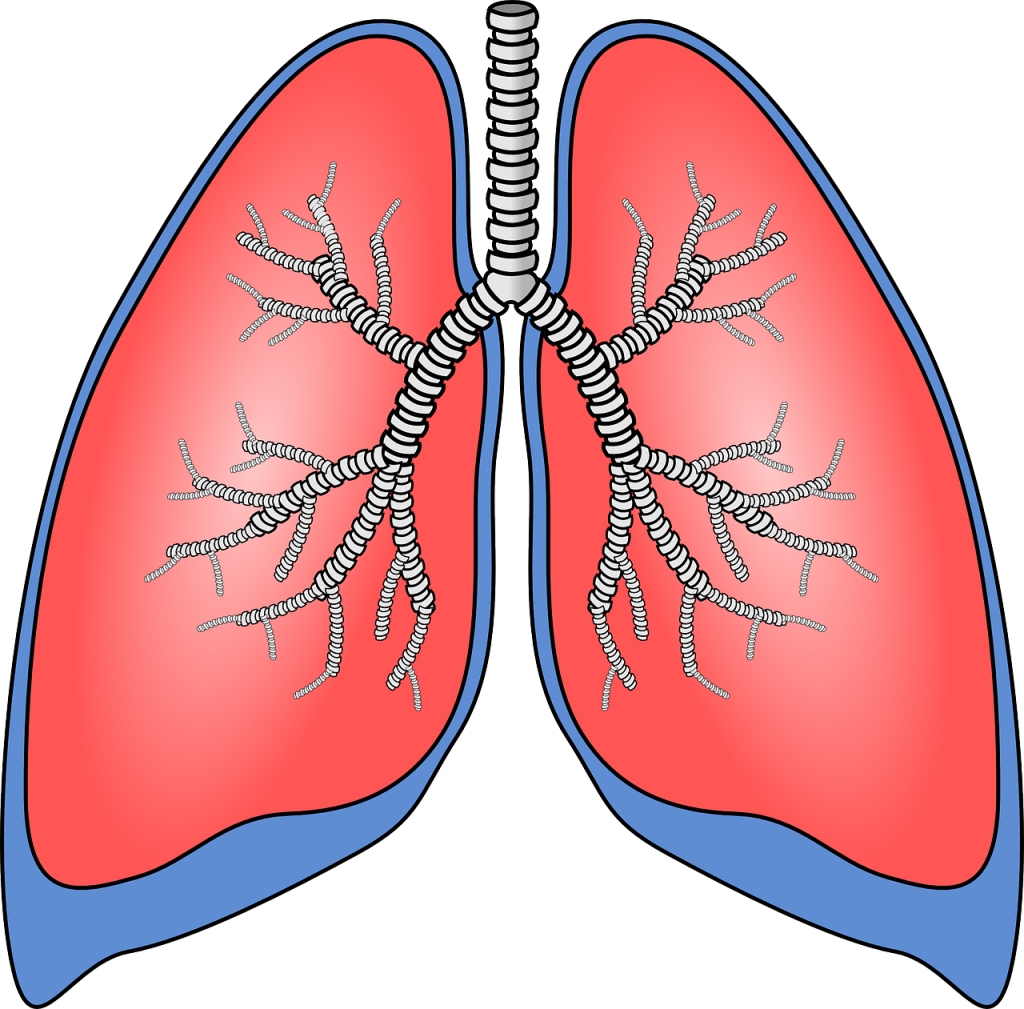

Bronş Ve Bronşcuklar

Soluk borusu akciğere girerken bronş adı verilen iki kola ayrılır.

Bronşlar akciğere girdikten sonra çok sayıda kollara ayrılır. Bu kolların her birine bronşçuk adı verilir. Bronşçukların ucunda alveol adı verilen hava keseleri bulunur.

AKCİĞER

Nefes alıp-verme yoluyla temiz havanın vücut içine alınmasını ve kirli havanın vücut dışına atılmasını sağlayan organlardır. Akciğerler, göğüs kafesi içinde yer alan pembe renkli, süngerimsi görünüşte organlardır. Akciğerler, sağ ve sol olmak üzere iki bölümden oluşur. Sol taraftaki akciğer, hemen altında kalp bulunduğu için daha küçüktür.

DİYAFRAM

Akciğerlerin çalışmasına yardımcı olan güçlü bir kastır. Diyafram, düzleşerek ya da kubbeleşerek hava giriş çıkışına yardımcı olur.

Akciğerlerin altında bulunan diyafram kası ve çevresindeki kaburgalar arası kaslar, soluk alıp verme esnasında kasılıp gevşer. Bu sayede akciğerler genişleyip daralır.